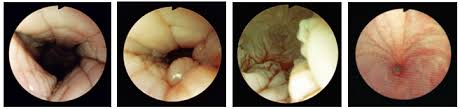

Artificial Insemination In Dogs Intechopen

Artificial Insemination In Dogs Intechopen from cdn.intechopen.com